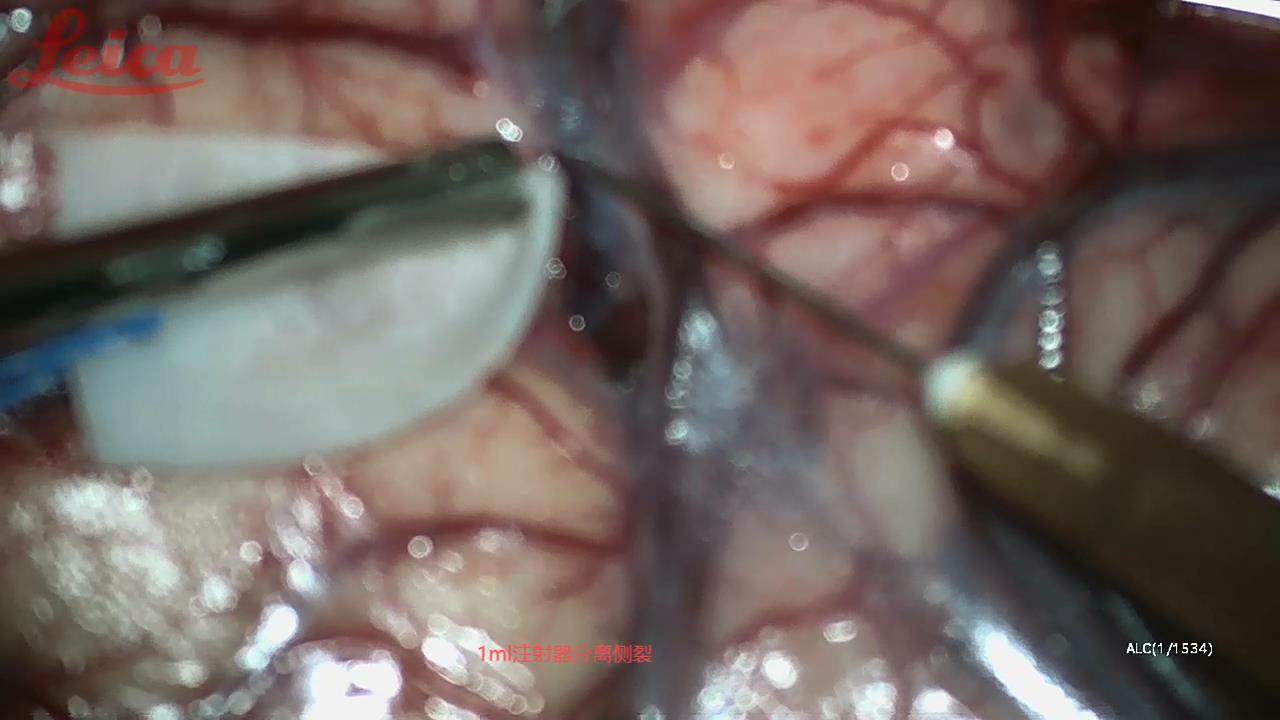

经外侧裂-岛叶造瘘清除血肿简要

经外侧裂-岛叶造瘘清除基底节出血